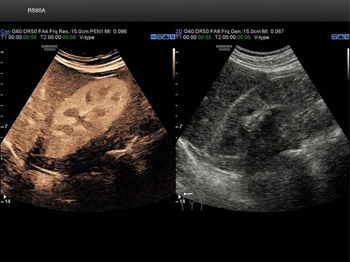

- Программно-технологический комплект 4D: рендеринг поверхности, визуализация полостей, мультипланарная реконструкция, MultiView для ультразвуковой томографии и ряд других функций

- Функция 3D Color

- Функция STIC: исследование сердца плода в режиме объёмной визуализации

- Функция STIC Color

- Функция Smart Sensor 3D для большей детализации исследования

Объемная визуализация сердца плода. Эта впечатляющая функция исследования сердца плода основана на достижениях технологии 4D и связана с пространственно-временной корреляцией получаемого вами изображения. Теперь вы сможете сохранять полученные данные для

Функция получения трехмерного изображения в режиме цветового допплеровского картирования. Эта функция поможет вам получить качественные трехмерные цветные изображения при проведении исследования. Нужного эффекта удается достичь за счет использования датчи

4D. Объемное сканирование в реальном времени больше не фантастика, а впечатляющее достижение современных технологий. С помощью сканирования этого типа вы сможете рассмотреть даже самые мелкие детали изображения под любым требуемым для проведения исследов